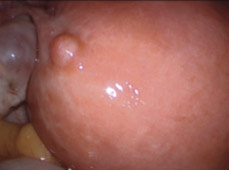

hirslanden-zysten-myom-und-gebaermutterentfernung-3

Abb. 3

Eierstockzysten: Operationsaufnahme des Ultraschallbefundes von Abb. 2